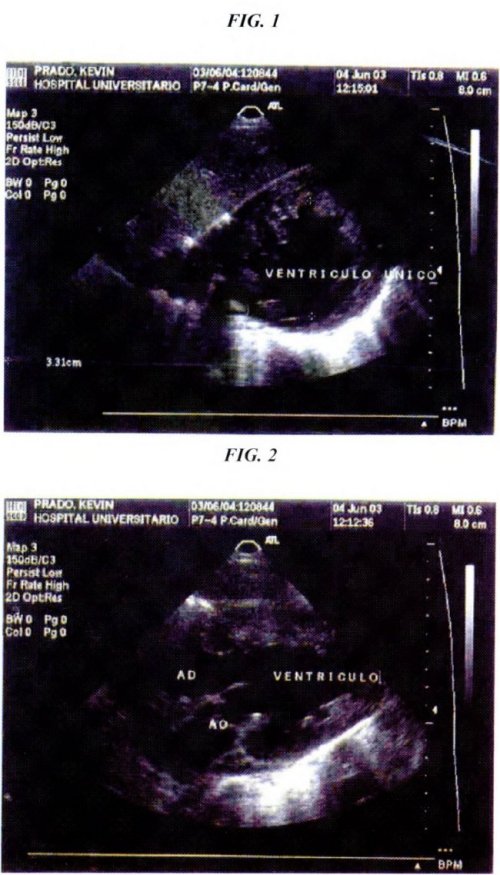

Eco-cardiografía: aurícula izquierda; dimensiones normales, función conservada, aurícula derecha; dimensiones normales, no se observan lesiones, ventrículo único (Fig. 1-2).